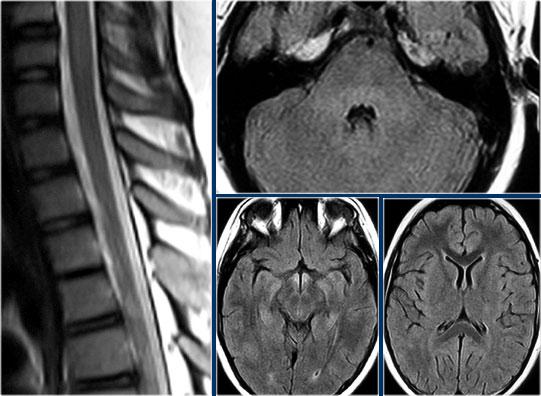

Đây là hình ảnh của một trường hợp TM điển hình.

Có tăng tín hiệu đa đoạn trên STIR và chuỗi xung T2W kèm theo phù nề nhẹ.

Phần lớn tủy sống trên đường kính ngang bị tổn thương.

Không có ngấm thuốc tương phản từ, đây thường là đặc điểm thường gặp trong TM.

Đôi khi có thể thấy ngấm thuốc dạng vá không đều.

Khi có ngấm thuốc tương phản từ, việc phân biệt TM với u tế bào hình sao (astrocytoma) có thể rất khó khăn.